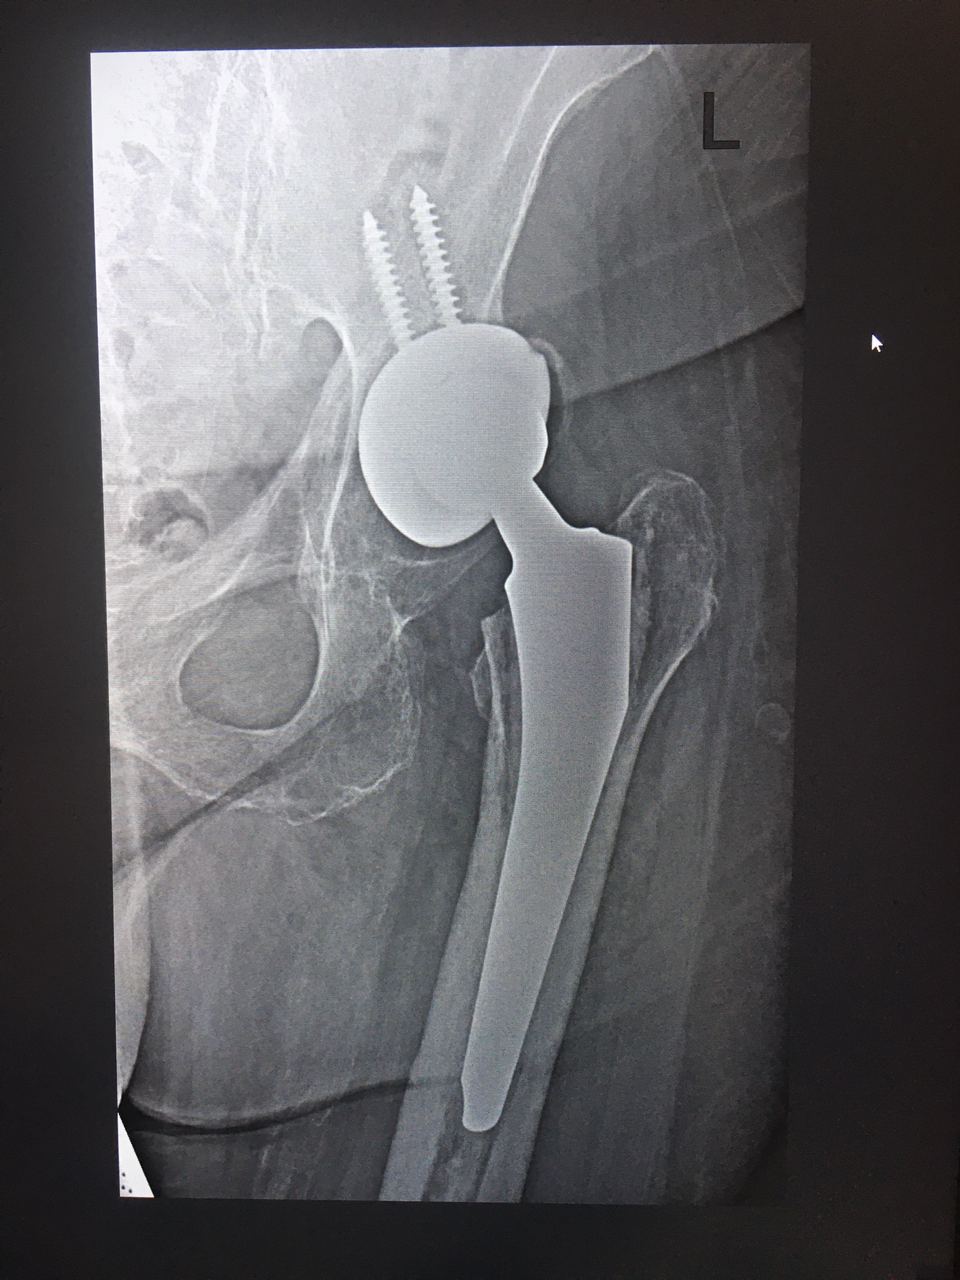

Помогите пожалуйста оценить, норм тут все или нет? Мне кажется тут неполное покрытие чашки эндопротеза

Никогда ещё не приходилось оценивать эндопротез 🙈